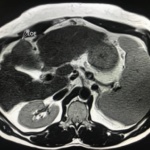

En el presente caso, encontramos una lesión típica de hepatocarcinoma en el segmento 5 ( hiperintensa en T2, restringe en la Difusión con ADC bajo. Realza heterogéneamente postcontraste EV, con wash out y presencia cápsula tardía).

El objetivo es identificar dentro de la multifocalidad de nódulos , un hepatocarcinoma precoz o de pequeño tamaño , cuando la posibilidad de tratamiento con intención curativa es viable , a pesar de la cirrosis.